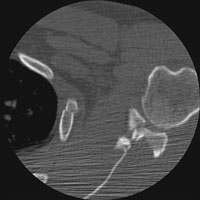

- Click on the image for a larger versionBAxial CT. This also shows the comminuted intraarticular fracture of the glenoid.